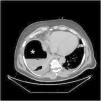

A 49-year-old male presented with no medical history apart from laparoscopic right renal cyst (Bosniak III-IV) removal performed a month ago. He presented to the emergency room with malaise, nonspecific abdominal pain and dyspnea. The initial chest radiographic study (Fig. 1) suggested pneumoperitoneum. The subsequent abdominal CAT scan (Fig. 2) revealed a subphrenic collection with an air-fluid level. Surgery confirmed retroperitoneal right colon perforation. Although retroperitoneal colon perforation is usually associated with retropneumoperitoneum and retroperitoneal abscesses, neither of these conditions were observed in the present case. The patient exclusively presented a subphrenic abscess with an air-fluid level, which additionally produced a false image of pneumoperitoneum on the chest x-ray examination.